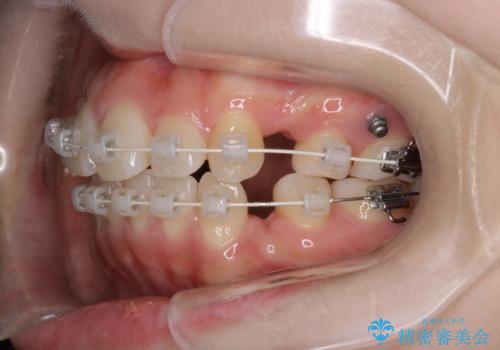

- 矯正装置

- 審美装置

- 治療計画

- 4番の歯を4本抜歯をし、上顎にマイクロインプラントを2本埋入し、遠心移動を行いました。